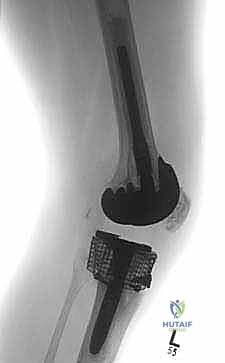

* الترقيع العظمي الهيكلي (Structural Allograft): استخدام كتل عظمية كبيرة مأخوذة من متبرع (بنك العظام) لتعويض فقدان عظمي كبير وغير محتوى. يتم تشكيل العظم ليطابق العيب بدقة. يتطلب هذا الخيار مهارة جراحية عالية لضمان التحام العظم المزروع بعظم المريض.

4. المخاريط والأكمام المعدنية المسامية (Porous Metaphyseal Cones & Sleeves)

هذه هي أحدث الثورات في عالم جراحة مراجعة المفاصل، وهي التقنية المفضلة لدى الأستاذ الدكتور محمد هطيف في حالات الفقدان العظمي الشديد (النوع الثاني والثالث من AORI). تُصنع هذه المخاريط من معادن عالية المسامية (مثل التنتالوم أو التيتانيوم المطبوع ثلاثي الأبعاد) التي تحاكي بنية العظم الإسفنجي.

تُزرع هذه المخاريط في التجاويف الكبيرة في قصبة الساق، وبفضل مساميتها العالية، ينمو عظم المريض الطبيعي داخل مسام المعدن (Osseointegration)، مما يوفر ثباتاً حيوياً وميكانيكياً هائلاً ومستداماً مدى الحياة.